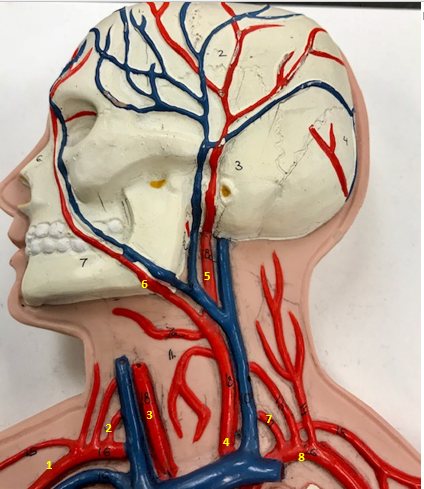

Right subclavian artery

Name #1

Supplies blood to right arm and shoulder

Function of right subclavian artery (1)

Right vertebral artery

Name #2

Supplies blood to brain and spinal cord

Function of right vertebral artery (2)

Right common carotid artery

Name #3

Supplies blood to right neck and head

Function of right common carotid artery (3)

Left common carotid artery

Name #4

Supplies blood to left neck and head

Function of left common carotid artery (4)

Left external carotid artery

Name #5

Supplies blood to face neck and skull

Function left external carotid artery (5)

Left facial artery

Name #6

Supplies blood to face and neck

Function of left facial artery (6)

Left vertebral artery

Name #7

Supplies blood to brain and spinal cord

Function of left vertebral artery (7)

Left subclavian artery

Name #8

Supplies blood to left arm and shoulder

Function of left subclavian artery (8)